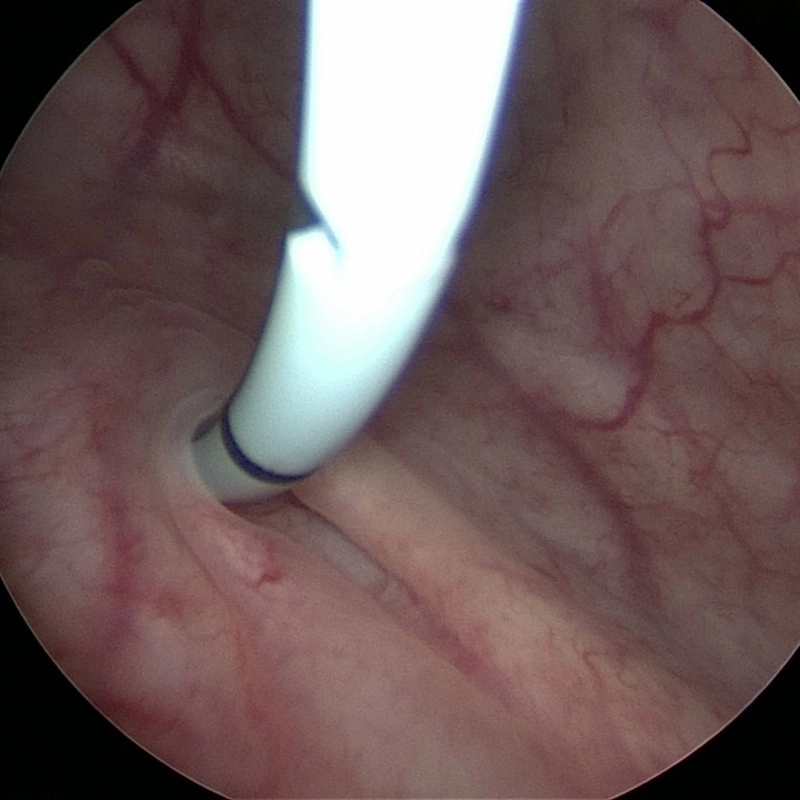

Сегодня врач выполняет более 300 операций в год.

• Лапароскопические операции: нефропексия, нефрэктомия, иссечение кист почек, пластика мочеточника (ЛМС), уретеролитотомия, нефролитотомия, холецистэктомия.

• Эндоскопические операции по аденоме простаты,

ТУР аденомы простаты (TURP).

• Контактная лазерная литотрипсия

(камней мочеточника, почек, мочевого пузыря).

• Прочие эндоскопические операции: аденомэктомия,

цистостомия, операции Бергмана, Винкельмана,

Лорда, варикоцелэктомия по Мармару.

Врач уролог-хирург Биарсланов Магомед впервые

в Дагестане выполнил лапароскопическую пластику

лоханочно-мочеточникого сегмента со стентированием.

Операции проводятся на современном оборудовании и под контролем

настоящего специалиста!